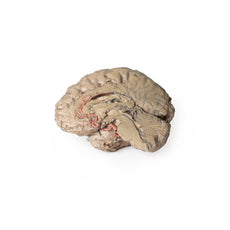

The head and neck of the specimen provides views of both superficial and deep structures in the region. The calotte has been removed ~2cm superior to the orbits to expose the brain in relation to the endocranial cavity. The transverse section through the cerebrum demonstrates the relation of the grey matter cortex to the white matter medulla, as well as the lateral ventricles with a small amount of choroid plexus visible in the base of both spaces. The skin and superficial fascia on the right side has been retained and false-coloured to display the angiosomes of the face and posterior neck. On the left side, the superficial tissues have been dissected to expose the muscles of facial expression, muscles of mastication, and deeper structures of the infratemporal fossa including the lingual nerve, terminal branches of the external carotid artery into the superficial temporal and maxillary arteries.

The head and neck of the specimen provides views of both superficial and deep structures in the region. The calotte has been removed ~2cm superior to the orbits to expose the brain in relation to the endocranial cavity. The transverse section through the cerebrum demonstrates the relation of the grey matter cortex to the white matter medulla, as well as the lateral ventricles with a small amount of choroid plexus visible in the base of both spaces. The skin and superficial fascia on the right side has been retained and false-coloured to display the angiosomes of the face and posterior neck. On the left side, the superficial tissues have been dissected to expose the muscles of facial expression, muscles of mastication, and deeper structures of the infratemporal fossa including the lingual nerve, terminal branches of the external carotid artery into the superficial temporal and maxillary arteries.